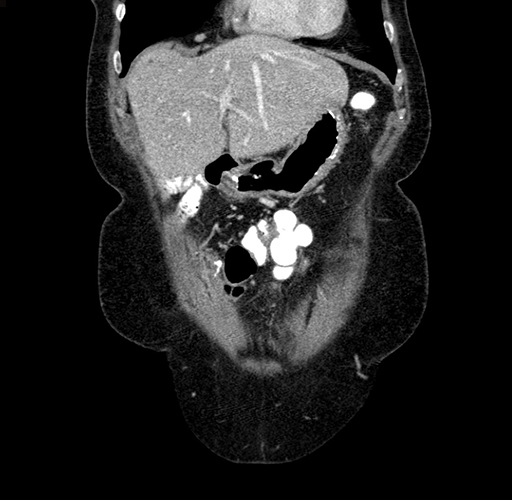

Pre-Chemo: Axial Venous

Axial Venous